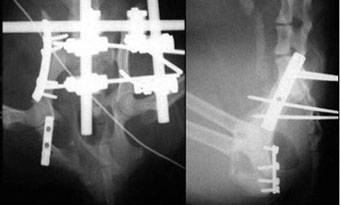

体重11kgの犬。

左側腸骨と坐骨で骨折していました。

腸骨はプレート法で、坐骨はプレート法とピンニングの併用で整復固定しました。

写真上段: 手術前

骨盤の一部が割れて内側に変位しています。

写真下段: 手術後 |